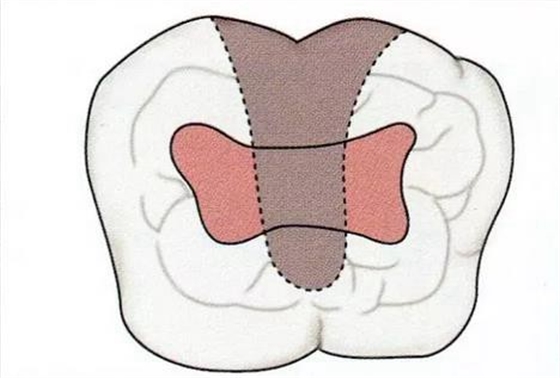

這是,分叉病變是否超出牙冠部1/3,成為了目標(biāo)之一。在這,我們介紹一下Kastenbaum所展示的判斷基準(zhǔn)。

▼圖19-1

圖19-1 未超過(guò)冠寬1/3的分叉部病變(II度),通過(guò)備牙改善食物的流向,形成便于清潔的形態(tài)。

▼圖19-2

圖19-2 分叉部病變超過(guò)冠寬1/3,即使進(jìn)行備牙也很難得到便于清潔的形態(tài),如果超過(guò)1/2的話,就不可能通過(guò)備牙來(lái)改變。這是就需要使用牙根分割進(jìn)行治療。

▼圖19-3

圖19-3 這種情況下,無(wú)法通過(guò)備牙進(jìn)行清潔,需要進(jìn)行分割。